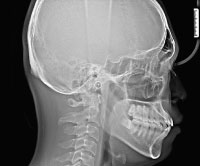

当院で使用する歯科用CTでは3次元=立体の情報を得ることができるため、歯だけでなく顎の骨・歯根の形態や、お口周りの神経の位置などがより正確に把握できます。CTで得た情報は正しい診断に役立つだけでなく、その情報を使って安全なインプラント手術を行うためのシミュレーションを行うことも可能になります。また、適切な矯正歯科治療の計画する行う上でも重要な「セファロ撮影」も可能です。

セファロとは「頭部X線規格写真」といって顎の形や上下の顎のズレ、歯の傾斜角、口元のバランスなどを長期的に管理するために撮影します。